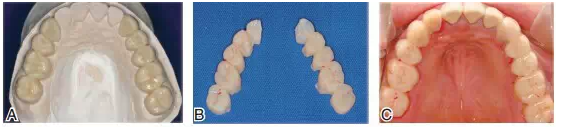

圖14根據(jù)診斷蠟型制作暫時(shí)冠戴入上頜。A.上頜后牙診斷蠟型;B.根據(jù)診斷蠟型翻制的暫時(shí)冠;C.暫時(shí)冠戴入口內(nèi)

圖15下頜基牙初預(yù)備,在口內(nèi)確定垂直距離,采取硅橡膠頜位關(guān)系記錄。將上頜通過面弓轉(zhuǎn)移上牙合架,確定上頜和顳下頜關(guān)節(jié)的關(guān)系,再通過頜位關(guān)系記錄,對(duì)合上下頜模型上牙合架

圖16雕刻下頜診斷蠟型(A),翻制下頜暫時(shí)冠并戴入口內(nèi)(B)。調(diào)整咬合接觸,暫時(shí)冠戴用兩個(gè)月,患者無顳下頜關(guān)節(jié)和咀嚼肌系統(tǒng)不適,并能確認(rèn)最適下頜位后,制作最終修復(fù)體